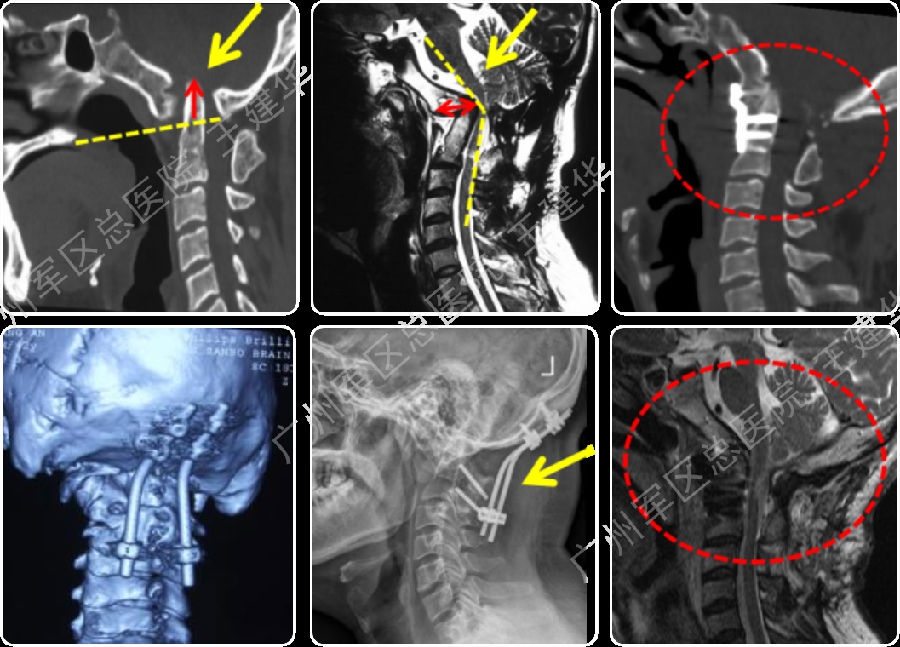

病例2

术前诊断

如何手术?

本例患者手术过程

手术前后对比

手术后CT显示,陷入枕骨大孔的齿突获得下拉复位

术后MRI发现,患者的颅底凹陷,脊髓空洞和Chiari畸形均获改善